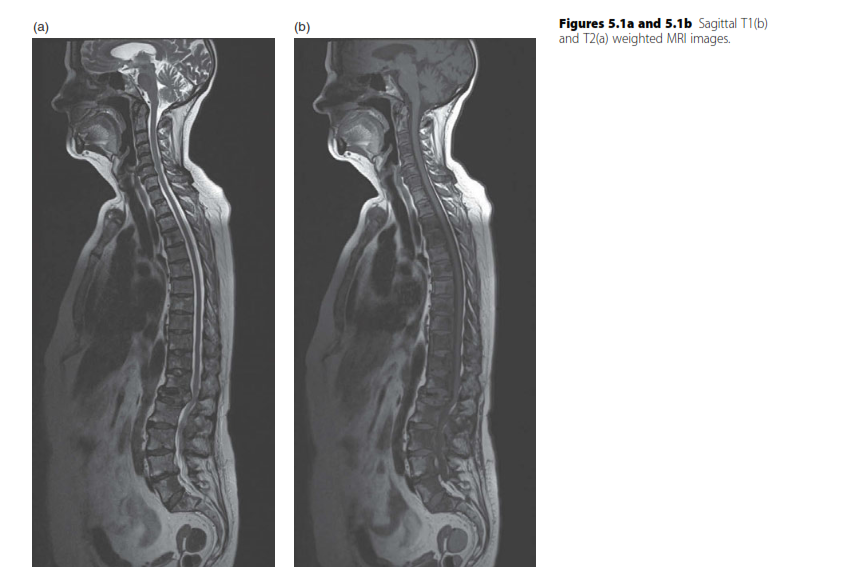

Spine structured oral questions5: Lumbar spinal stenosis and cervical myelopathy EXAMINER : A 70-year-old lad…